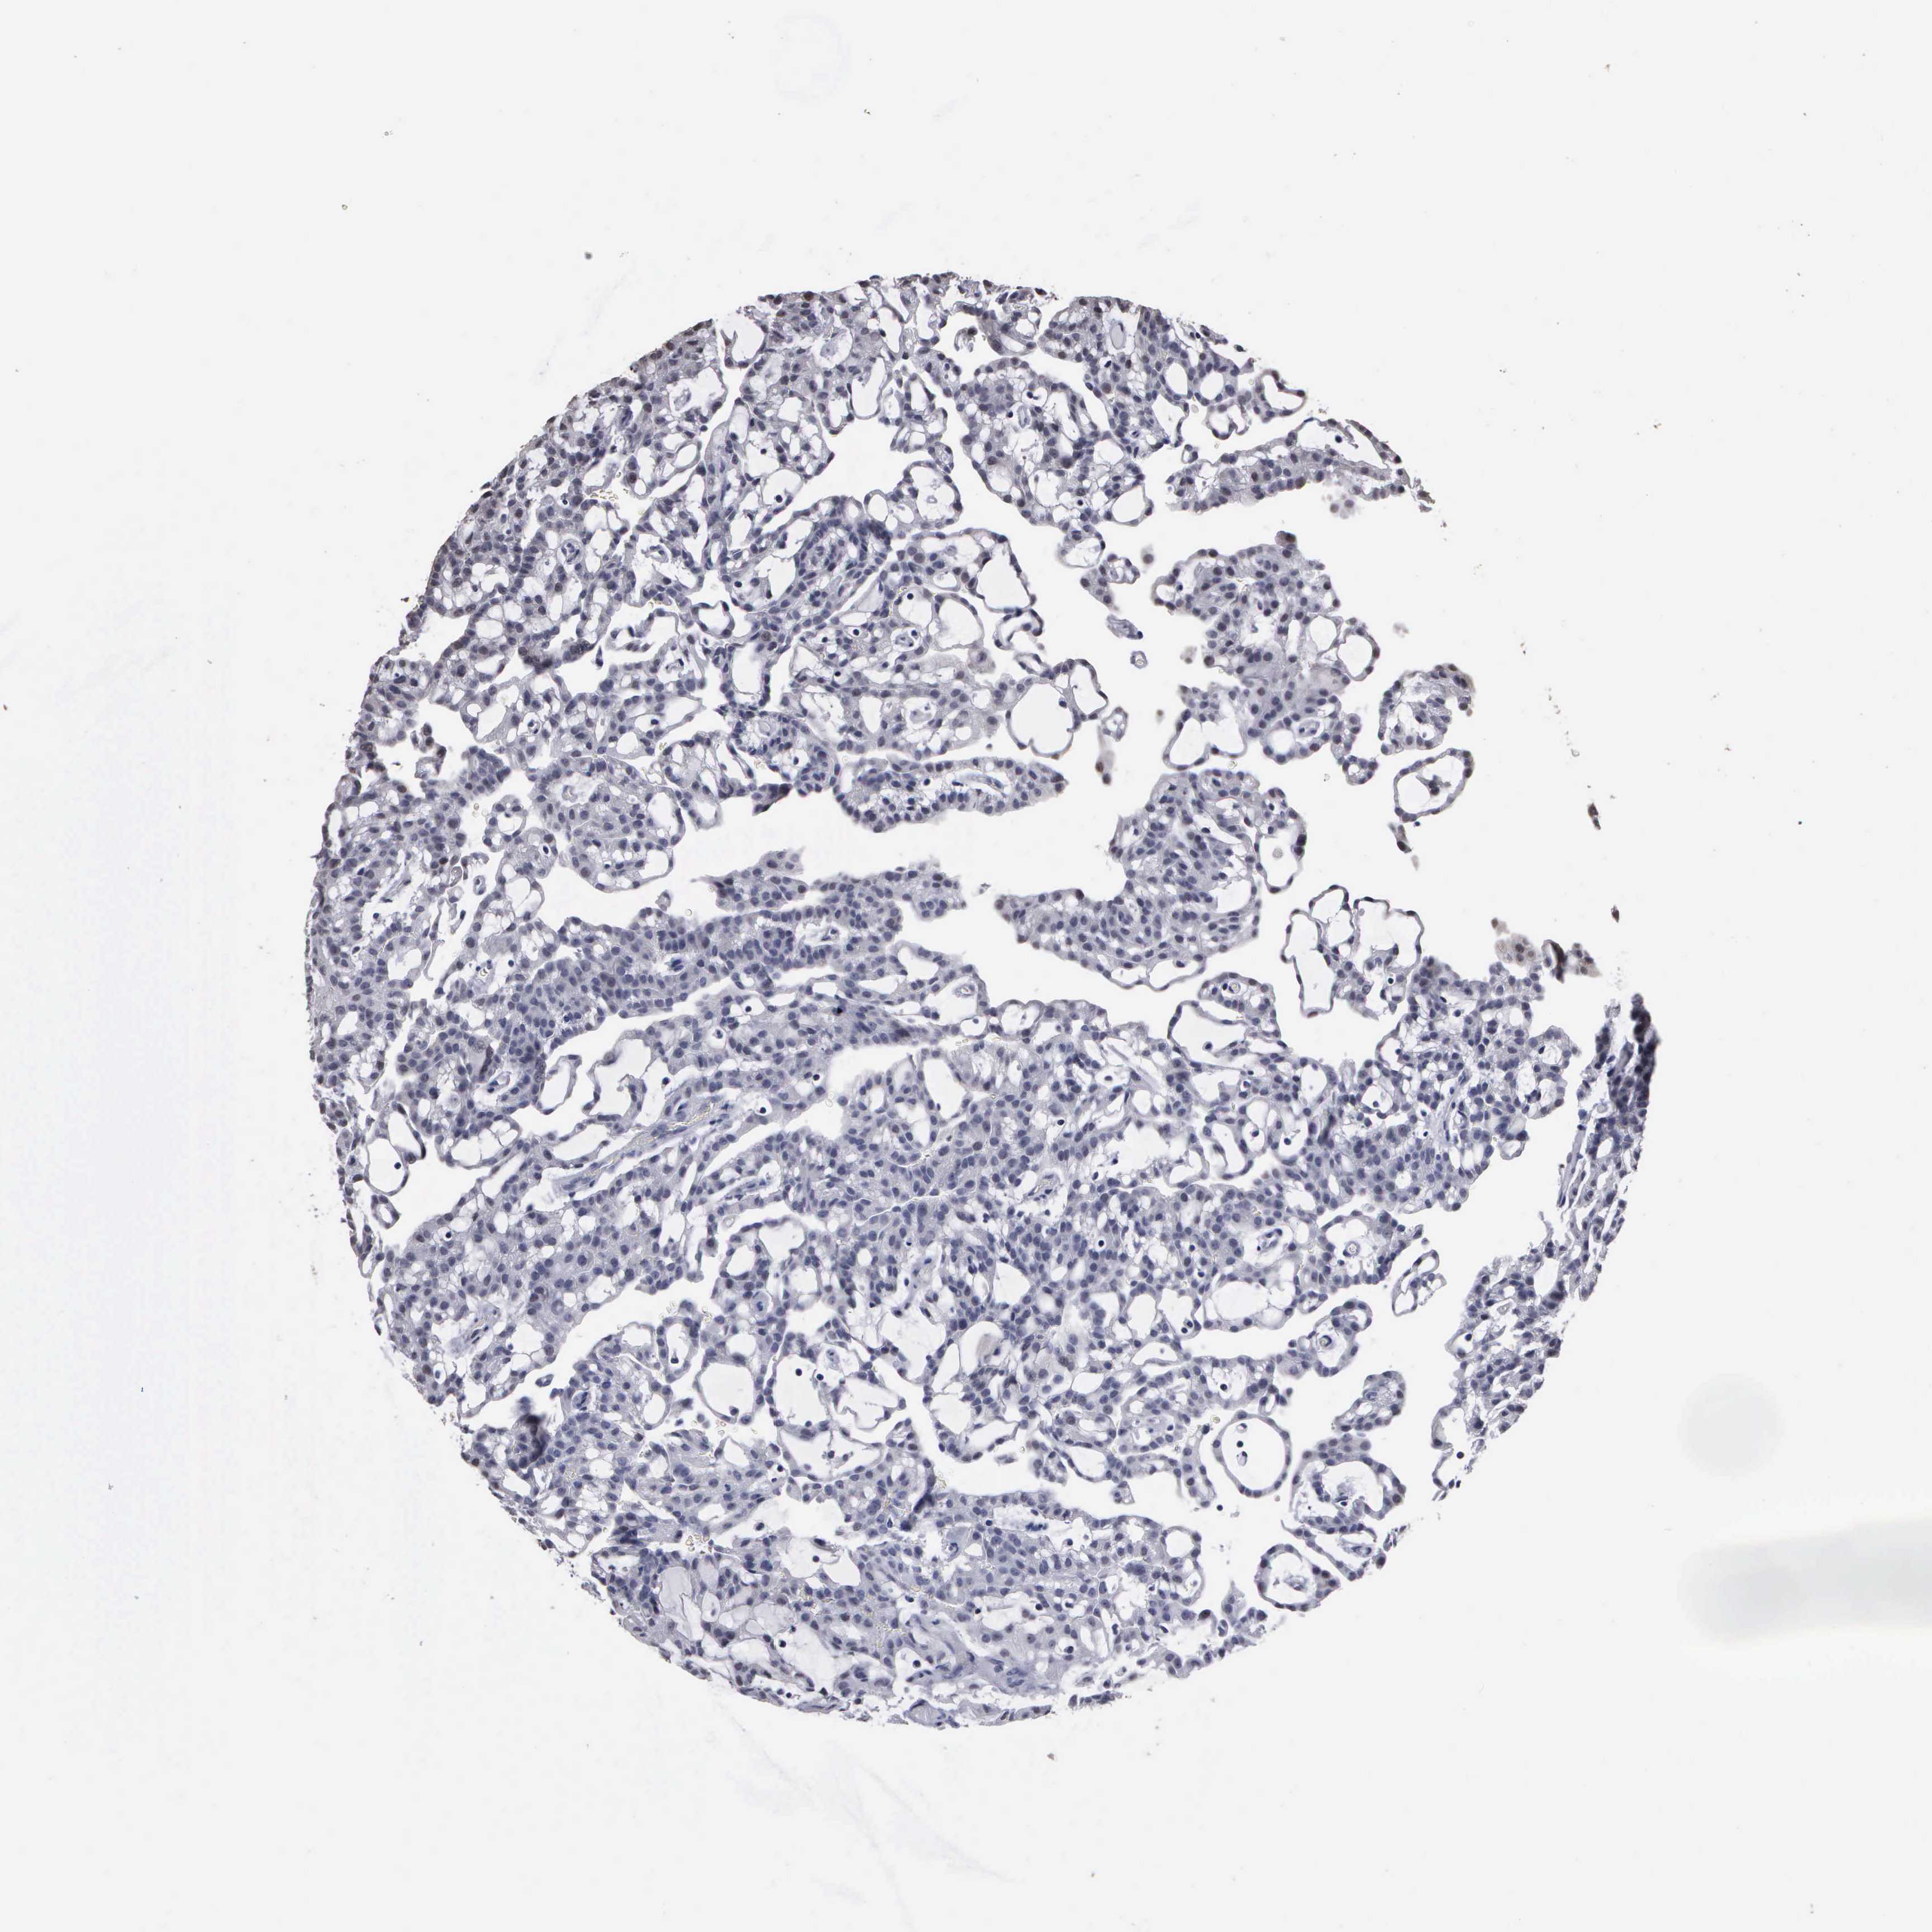

CANCER RENAL CANCER Show tissue menu

KICH TCGA KIRC TCGA KIRC VALIDATION KIRP TCGA PROTEIN RCC CPTAC PROTEIN EXPRESSION